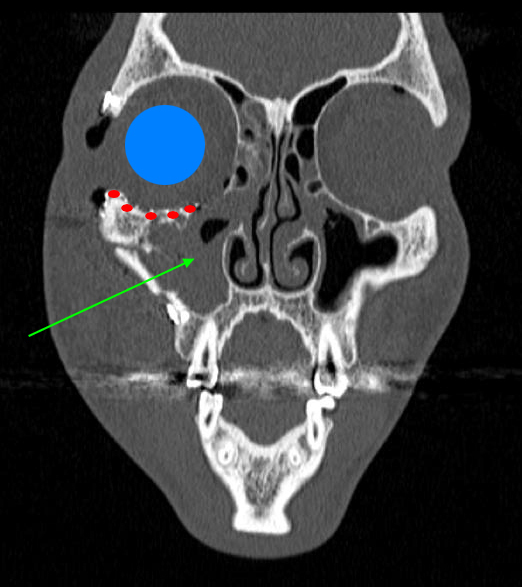

De garde, vous êtes appelé en salle de surveillance post-interventionnelle (SSPI) dans votre hôpital où vient d'être admis un patient conduit sur place par le service d'aide médicale d'urgence (Samu). Il s’agit d’un jeune homme de 20 ans, Monsieur D. Il aurait été victime, entre autres, d’un tir de Flash-Ball lors d’une rixe. Le projectile l’a atteint au niveau de la pommette et de l’orbite droites. Il présente une plaie de la région jugale haute, un œdème des paupières supérieure et inférieure. Vous ne visualisez pas le globe oculaire spontanément. Il est hémodynamiquement stable.

Traumatisme orbitaire = à risque de fracture des parois de l’orbite et donc d’incarcération d’un muscle oculomoteur.